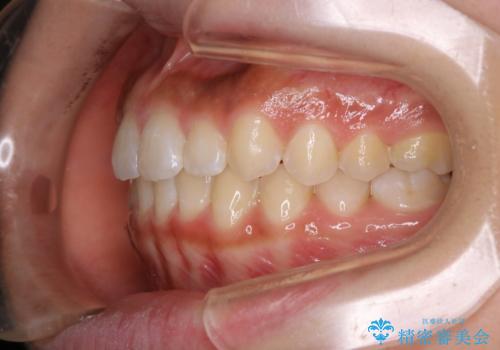

短期間ですきっ歯を改善:インビザラインLite

- 上の歯がすきっ歯なのと、歯が出ている気がするとご相談にいらした方です。

奥歯の噛み合わせに大きな問題がなく、患者様のご希望もあったため、前歯部メインで治療するインビザラインLiteで治療を行いました。

横顔のシルエットが改善し、口元もスッキリとなりました。